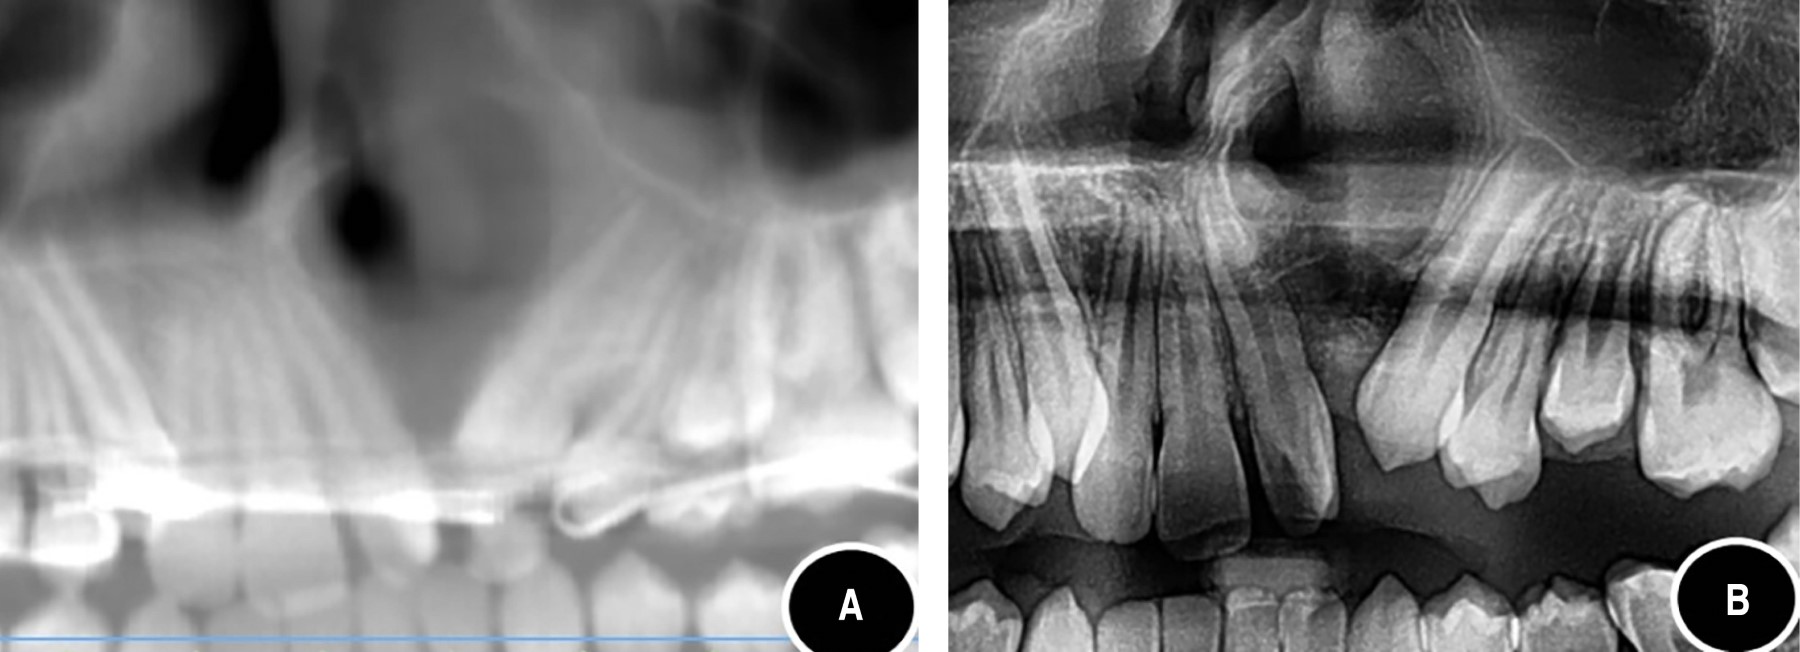

Figure 1

Figure 2

Figure 3

Figure 4

Figure 5

Figure 6

Figure 7